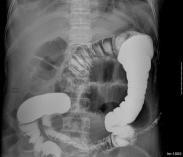

KUB平片:顯示腎實(shí)質(zhì)內(nèi)呈簇狀,放射狀或多數(shù)性粟粒狀排列的鈣化和結(jié)石。

IVU:顯示腎盂腎盞正常或腎盞增寬,杯口擴(kuò)大突出,于其外側(cè)見到造影劑在擴(kuò)大的腎小管內(nèi)呈扇形、花瓣?duì)睢⑵咸汛疇詈丸偳稜铌幱埃仪婚g不相連。由于結(jié)石密度不均勻,邊緣不整齊,環(huán)繞于腎盂腎盞周圍的多數(shù)囊腔似菜花狀。腎功能不佳者可行大劑量靜脈點(diǎn)滴尿路造影,能更清晰地顯示上述特征。逆行腎盂造影對診斷的作用不大。